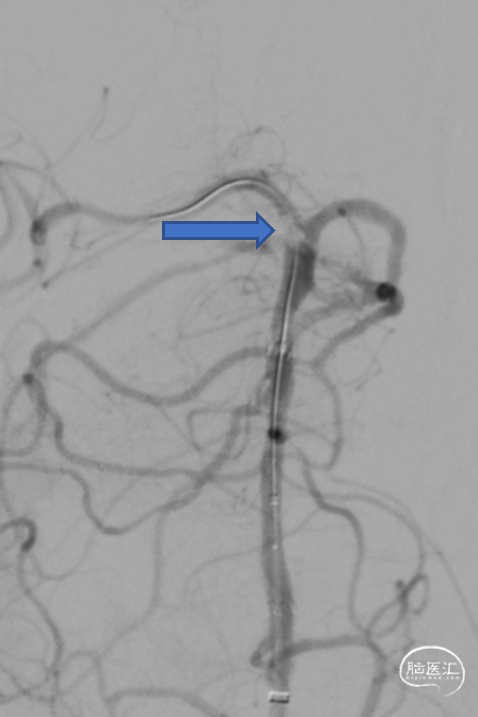

急诊DSA:Ⅱ型弓,基底动脉AICA以远未见显影。

加奇Tethys®中间导引导管到位,明确既往支架位置。但中间导管通过困难。